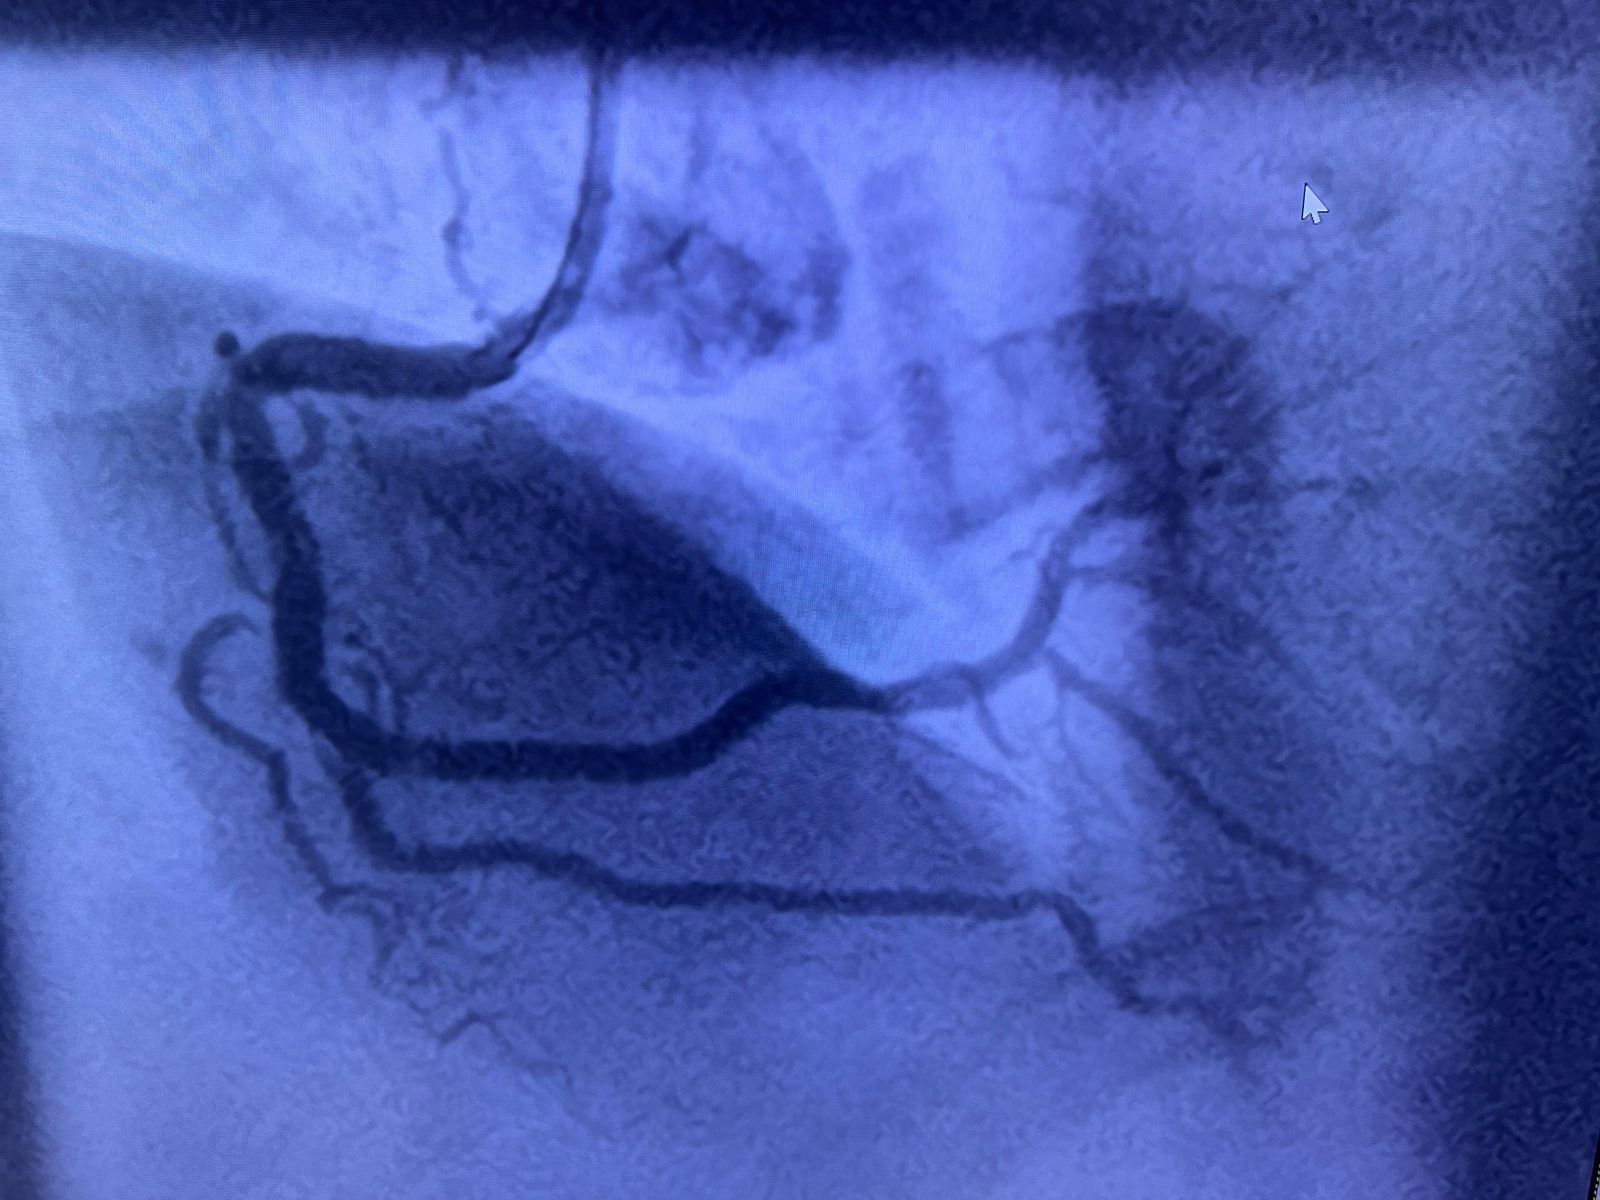

Deepa Kannan Hospital Heart Care Center & Cath Lab stands as a beacon of excellence in cardiovascular medicine. With state-of-the-art catheterization laboratory facilities and a team of renowned cardiac specialists, we are committed to providing comprehensive heart care services that combine cutting-edge technology with personalized patient care.

Our mission is to deliver exceptional cardiac care through innovative treatments, advanced catheterization procedures, interventional cardiology and compassionate patient support. We believe that every heartbeat matters and we're dedicated to ensuring yours beats strong and healthy for years to come.

State-of-the-art cardiac catheterization laboratory with advanced imaging technology